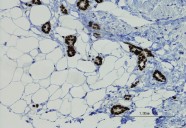

A team of investigators at Penn State College of Medicine reports the development of a new method that improves the mapping of genetic variants that influence the risk of neurodegenerative diseases. The method, published in Nature Communications , was created in response to long-standing challenges in connecting genome-wide association study data to specific changes in gene expression within the brain. The researchers sought a new approach because conventional bulk tissue studies mix many cell types together, and available single-cell datasets, although more precise, are small—especially for rare brain cell types that play important roles in conditions such as Alzheimer’s disease and amyotrophic lateral sclerosis (ALS) .